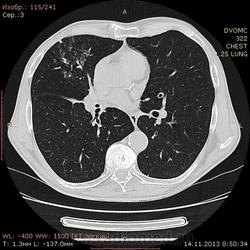

Пациент 76 лет. Жалобы на кашель в течение недели. На флюшке неоднородное интенсивное снижение пневматизации S8-10, уменьшение в объёме и однородное снижение пневматизации средней доли справа.Направили на КТ. Мои мысли - ателектаз средней доли справа с воздушной бронхографией. В S3, 8-10 облитерибующий бронхиолит с организующейся пневмонией или интерстициальный пневмонит? или бронхопневмония? Как ЭТО назвать....помогите...а?:-)

Думаю, что в переднем и в верхушечном сегменте верхней доли фиброз. Есть обрыв B7 с субсегментарным ателектазом дистальнее обрыва. Вот причину этого обрыва и ателектаза четко не вижу, возможно, что тут эндобронхиальная опухоль, добро- или злокачественная, либо бронх забит вязкой мокротой. Среднедолевой бронх и его ветви проходимы, и получается фиброателектаз средней доли. Бронхи 10-го сегмента заполнены секретом, в виде такой колбасы, ветвящейся соответственно бронхам. В S8 выражен фиброз, утолщен парасептальный интерстиций, слабо выраженное матовое стекло перибронхиально и по типу мягких внутридольковых очагов + та же колбаса участками. Убедительных признаков КОП, карциноматоза я не вижу, либо плохой танцор. У меня сложилось впечатление очаговой пневмонии, примущественно в S8, а уж по клинике - начало или разрешение. Субплевральные узелки всегда вызывают у меня вопросы, они могут быть как метастазами, так и неспецифическими узелками, не имеющими никакого значения. Грубого поражения верхних долей, кроме небольшого фиброза, я не вижу. Общая картина неоднозначна, я б сделала КТ-контроль после курса противовоспалительного лечения, недели через 3-4.

В заключении написала бы так: фиброателектаз средней доли, картина очаговой сегментарной пневмонии в S8 справа, субсегментарный ателектаз S7 справа (показана бронхоскопия для исключения эндобронхиального образования B7 справа).

помимо сказанного добавил бы центрилобулярные узелки,утолщенный центральный перибронховаскулярный интерстиций , локализация узелков ближе к корням.добавлю саркоидоз односторонний стадия 2

Коллеги, а как вам внутригрудные лимфоузлы? Особенно бифуркационные...

Субкаринальный увеличен, 12х18х25 мм, но с учетом пневмонии - почему нет, воспалительная лимфаденопатия. Количественно увеличены ВГЛУ, с сохранением бобовидной формы.